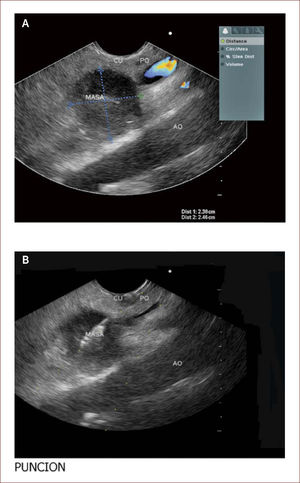

Paciente con seudoquistre del páncreas posterior a cuadro de pancreatitis aguda. La paciente tuvo dolores que no fueron rotulados como tal y los manejaron en el campo (Fundo), como algo digestivo. Al consultar en la capital a una clínica encuentran en la TAC esta lesión. En la imagen A se ve la medición del tamaño del quiste y en la imagen B el grosor de la pared de 6mm. En la C a la izquierda el contenido líquido con pocos detritus. Fue llevada a drenaje y colocacion de stent.